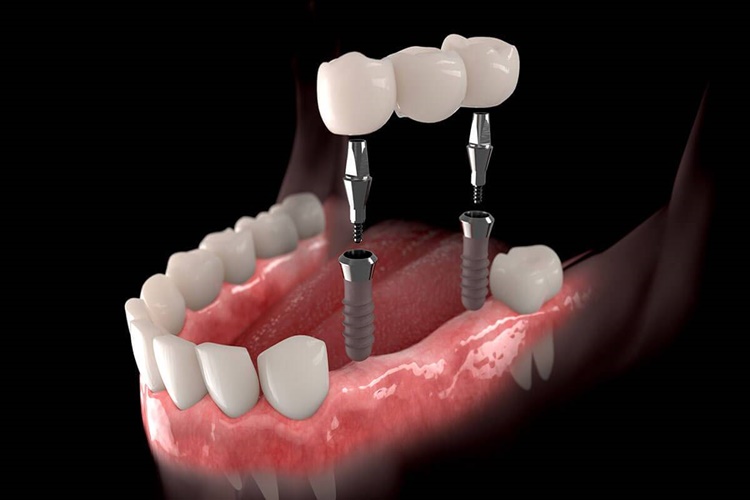

İmplant Ücretini Devlet Karşılıyor Mu?

İmplant Ücretini Devlet Karşılıyor Mu?

Genellikle implant tedavileri devlet sağlık hizmeti

kapsamında karşılanmayan özel bir diş tedavisidir. Ancak bazı ülkelerde ve bazı

özel durumlarda implant tedavisi için belirli sağlık sigortası planları veya

kamu destekli programlar bulunabilir. Bu nedenle implant tedavisi için devlet

tarafından karşılanıp karşılanmadığını öğrenmek için yerel sağlık otoriteleri

veya sağlık sigortası kuruluşlarıyla iletişime geçmeniz gerekebilir.

Ancak çoğu durumda implant tedavisi özel bir diş tedavisi

olarak kabul edilir ve hastalar tarafından kendileri veya özel sağlık

sigortaları tarafından finanse edilir. İmplant tedavisi düşünüyorsanız, önce

diş hekiminizle görüşerek tedavi seçenekleri ve maliyetleri hakkında ayrıntılı

bilgi almanız önemlidir.